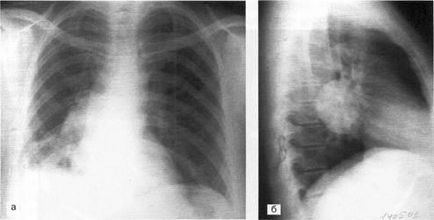

Caracteristica umbră inel închis cu pereți groși și o circulară decolorat în interior, de multe ori în combinație cu întunecare partea inferioară a formațiunii, nivelul separat orizontal de iluminare (fluid la interfața cu aer) da formarea parenchimului pulmonar cavitară în prezența posturilor cavitate cu aerul exterior. Formarea unor astfel de goluri tipice de abcese pulmonare (figura 2), și prezența în interiorul cavității blocări - abcese gangrenoasă (Figura 3) sunt drenate prin arborele bronsic.

Fig. 2. Roentgenograma pacientului K. 38 ani, în proiecțiile laterale (a) și laterale (b). În S6 a plămânului drept, este definită o umbră inelară închisă cu pereți groși - o cavitate umplută cu lichid (2/3 din volumul cavității) cu un nivel orizontal și aer. Abcesul plămânului drept, parțial drenat prin bronhii